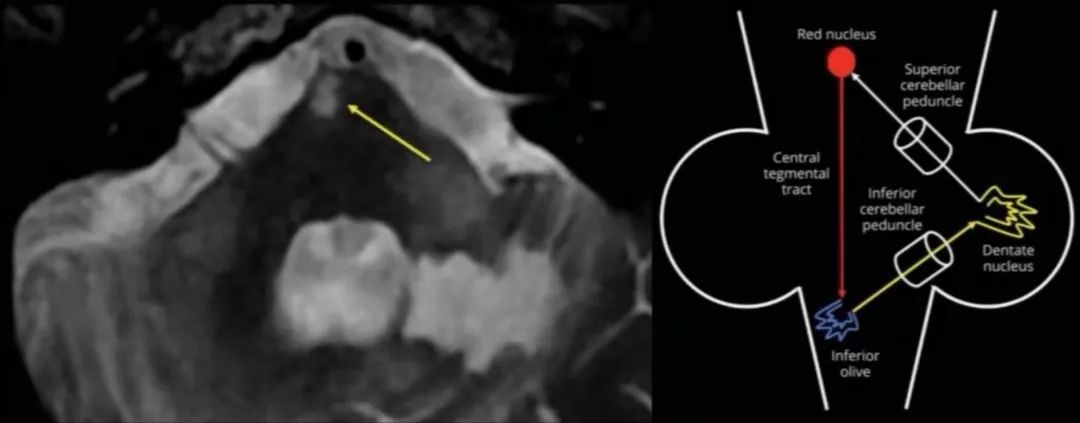

女性,91岁,房颤(未抗凝治疗),高血压,肥胖。急诊入院时NHISS:24;mRS:3级。考虑为左侧大脑中动脉闭塞综合征;20分钟内接受了Ⅳ型纤溶酶原激活剂治疗,症状未见明显改善,后行CTA检查显示:左侧M1段高度狭窄,左侧A1段近端有一个小突起,提示有动脉瘤或闭塞的AMC。急诊DSA证实:左AMCAM1段闭塞,AMCA与近端A1节段呈尖锐的夹角(见图A);同时伴MCA中段的狭窄。根据AMCA的解剖结构、小口径和潜在的狭窄,采用静脉血栓抽吸术,并进行了血管再通治疗(见图B、C)。

答案:副大脑中动脉闭塞。

大脑中动脉变异包括有孔型大脑中动脉、副大脑中动脉、重复大脑中动脉。有学者提出,用“副大脑中动脉”来描述一个异常的起源于大脑前动脉的大脑中动脉;而“重复的大脑中动脉”是指起始于脉络膜前动脉和颈内动脉分叉间的大脑中动脉。有时严格鉴别副大脑中动脉和重复大脑中动脉非常困难。当大脑中动脉闭塞时,副大脑中动脉的管径、供血区域范围、侧支代偿程度决定了副大脑中动脉能不能成为潜在的侧支血供来源以避免大面积脑梗死,因为副大脑中动脉的侧枝代偿有时并不充分。而且副大脑中动脉本身也可出现狭窄甚至闭塞而引起缺血性脑血管病事件。